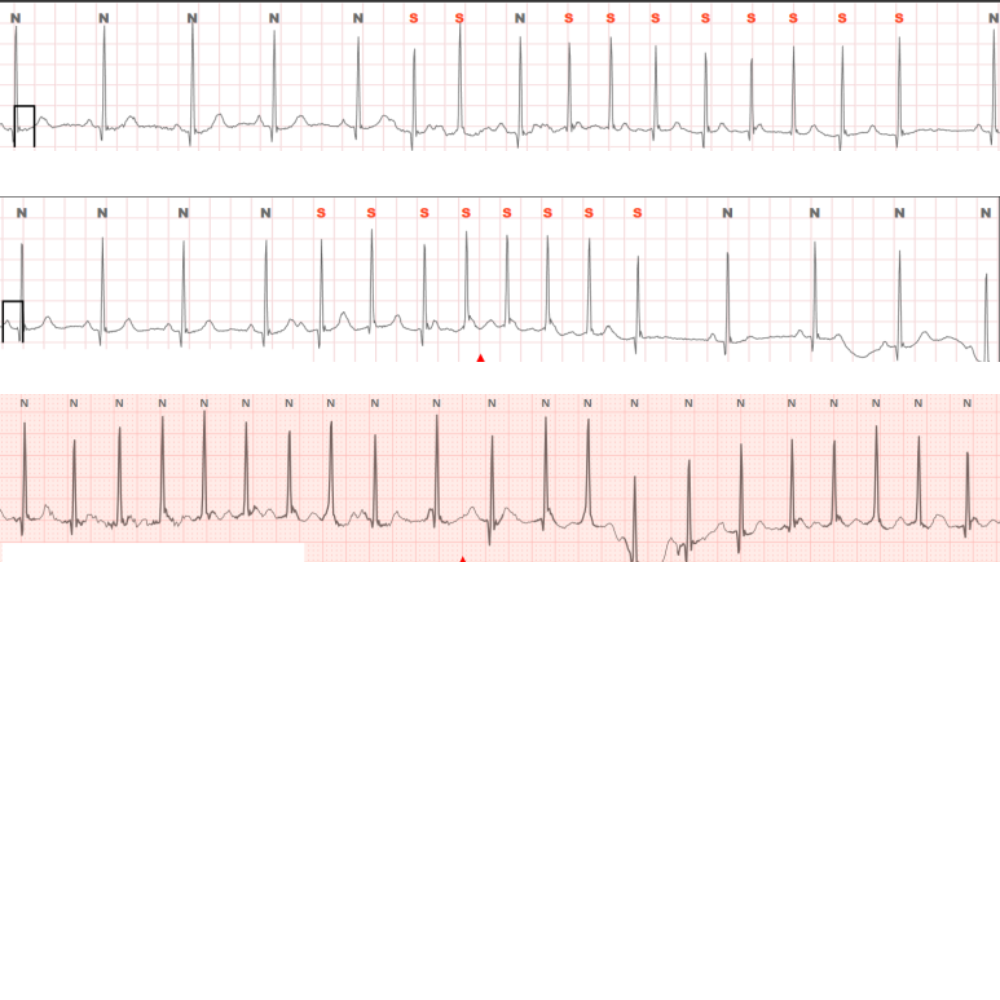

대표적인 원인 중 하나는 심장의 전기신호 전달에 문제가 생기는 부정맥으로,

맥박이 너무 빠르거나 불규칙해질 수 있습니다.